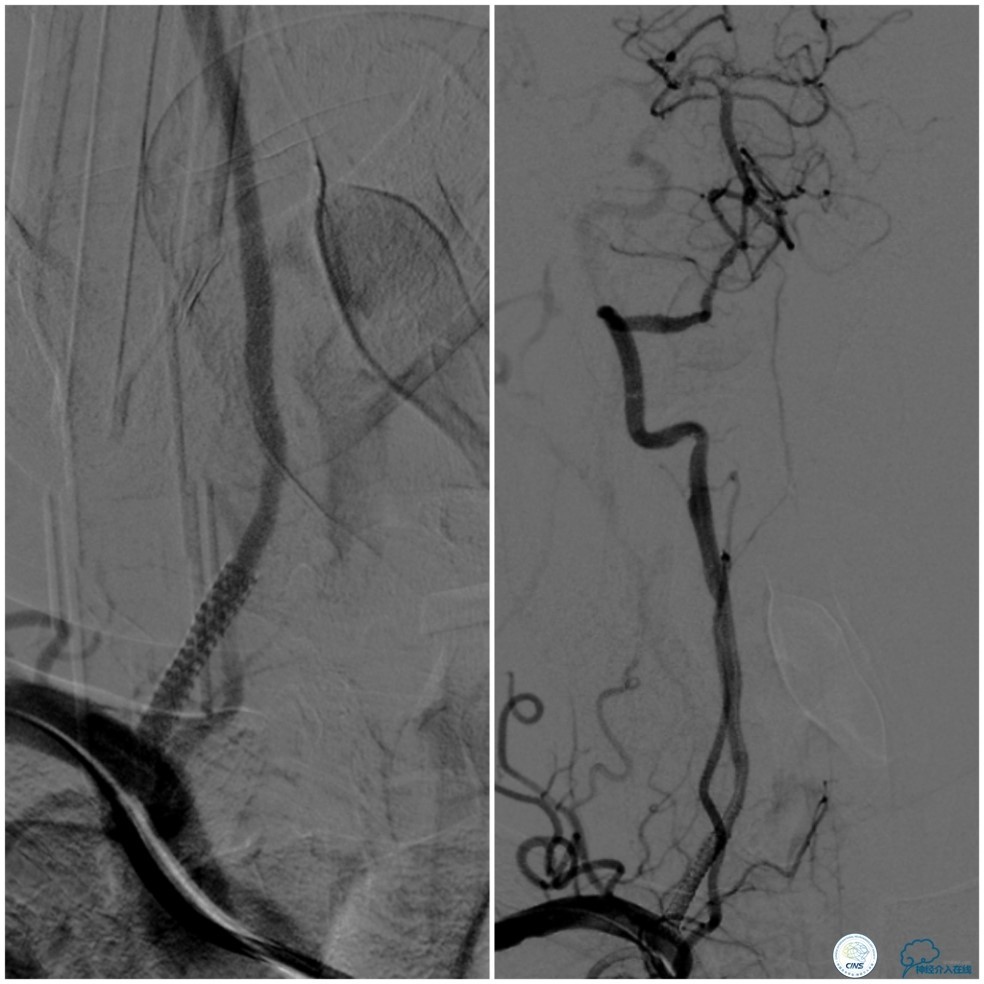

缓慢回撤6F导引导管至锁骨下动脉,造影显示右椎V1段支架无移位,前向血流正常(图17)。

图17